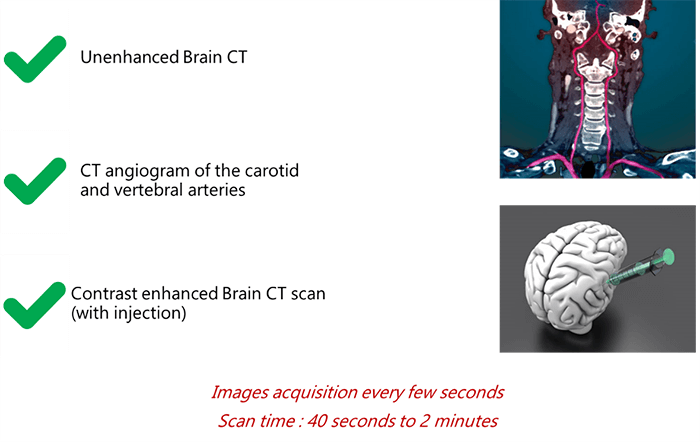

To begin, the scan protocol may be divided into 3 main parts:

- The technologist starts the exam with an unenhanced CT (without contrast injection)

- At this level, a CT angio for the carotids and vertebral arteries is recommended

- After injection of the contrast, a new acquisition of the CT is done where images are acquired every few seconds to see the real-time trajectory of the contrast in the brain vessels